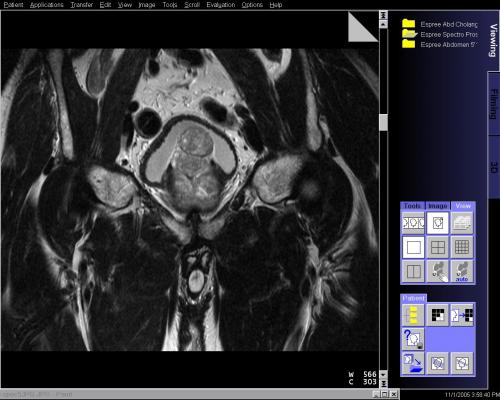

The designation is based in part on three-year follow-up data from a Phase III prospective, randomized clinical trial involving the use of SpaceOAR hydrogel, a technology developed by Augmenix to reduce the risk of rectal injury in men receiving prostate cancer radiation therapy (RT) by acting as a spacer that pushes the rectum away from the prostate during treatment.

SpaceOAR hydrogel reduces rectal injury in men receiving prostate cancer radiation therapy by acting as a spacer – pushing the rectum away from the prostate. This space between organs decreases the radiation dose to the rectum and other organs at risk (OAR). Earlier this year, Augmenix announced published data from their prospective, randomized clinical trial showing that patients treated with SpaceOAR hydrogel prior to prostate cancer radiotherapy demonstrated significant rectal (bowel), urinary and sexual benefits through three years of follow-up.